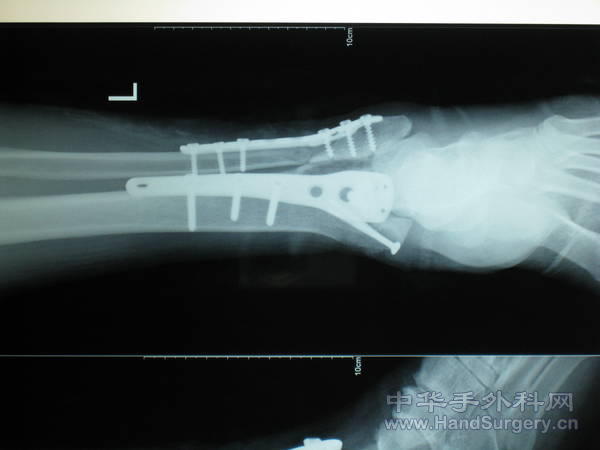

pilon骨折一例-手足外科魏宝富主任作品

这种骨折为从高坠落高能量致的损伤,损伤都较重,对重的有的主张一期行关节融合,如轻的可以行复位内固定,一般都要行植骨。

楼主的手术做得很好,创伤性关节炎可能是再所难免了。

pilon骨折在哪做都是高难度手术,骨性支架的建立应该最重要,皮肤缺损对手足外科大夫来讲已经不是什么难题 ,希望看到踝关节关节面的x线或ct。

魏主任:你的手术做的很好,但是不知关节面是如何处理的,植骨了吗?是急症做的还是消肿以后做的?切口愈合如何?还有外侧的关节面好像没有处理?

胫骨远端外侧解剖钢板过前,如果锁定钢板会好很多,植骨不知道什么情况

对于此类骨折,手术最关键所在应该是先恢复腓骨解剖位置,其余骨折块做起来较容易些。另外需要注意植骨支撑,再者注意下胫腓关系一定要稳定!不要轻易去做融合!个人理解